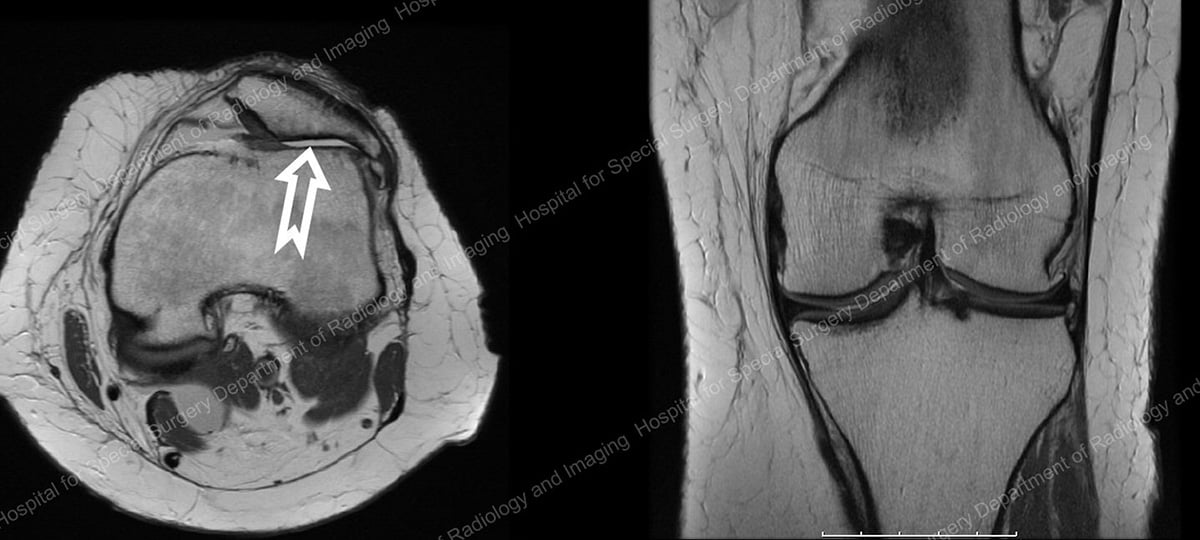

MRI images of a 47-year old patient, demonstrating well-preserved medial and lateral compartments but severe arthritis in the patellofemoral compartment, shown behind the patella (kneecap) at the end of the white arrow.